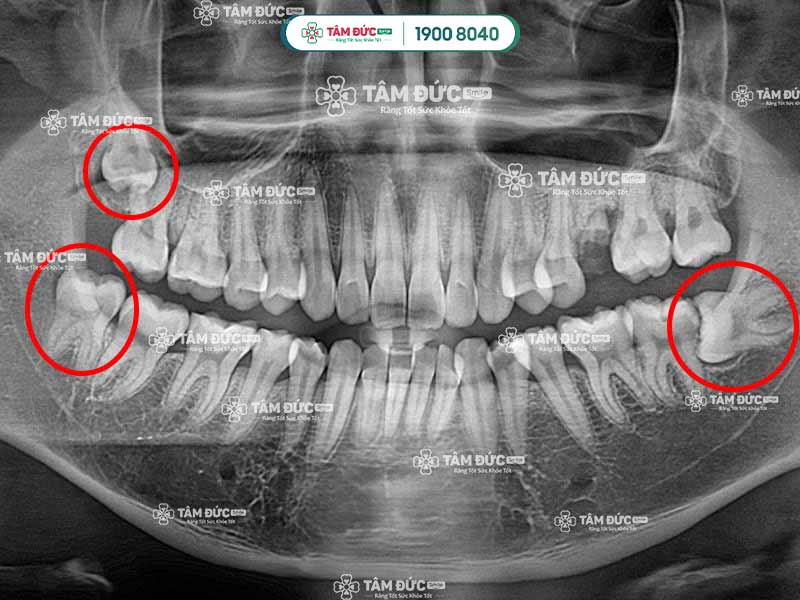

Trên cung hàm, răng khôn là chiếc răng số 8, mọc sát vách hàm và nằm ở trong cùng hàm răng. Răng khôn mọc sát răng số 7, Quý khách sẽ có 4 chiếc răng khôn chia đều cho cả hàm trên và dưới.

Răng số 8 sẽ gây đau trong các trường hợp mọc ngầm, mọc lệch, mọc đâm vào răng số 7,... Mặt khác, sự phát triển của răng khôn cũng làm cho bề mặt nướu bị phá vỡ, từ đó gây đau nhức dai dẳng. Sở dĩ mọc răng khôn gây đau vì lúc này xương hàm đã phát triển hoàn thiện, không đủ chỗ cho răng khôn mọc lên.